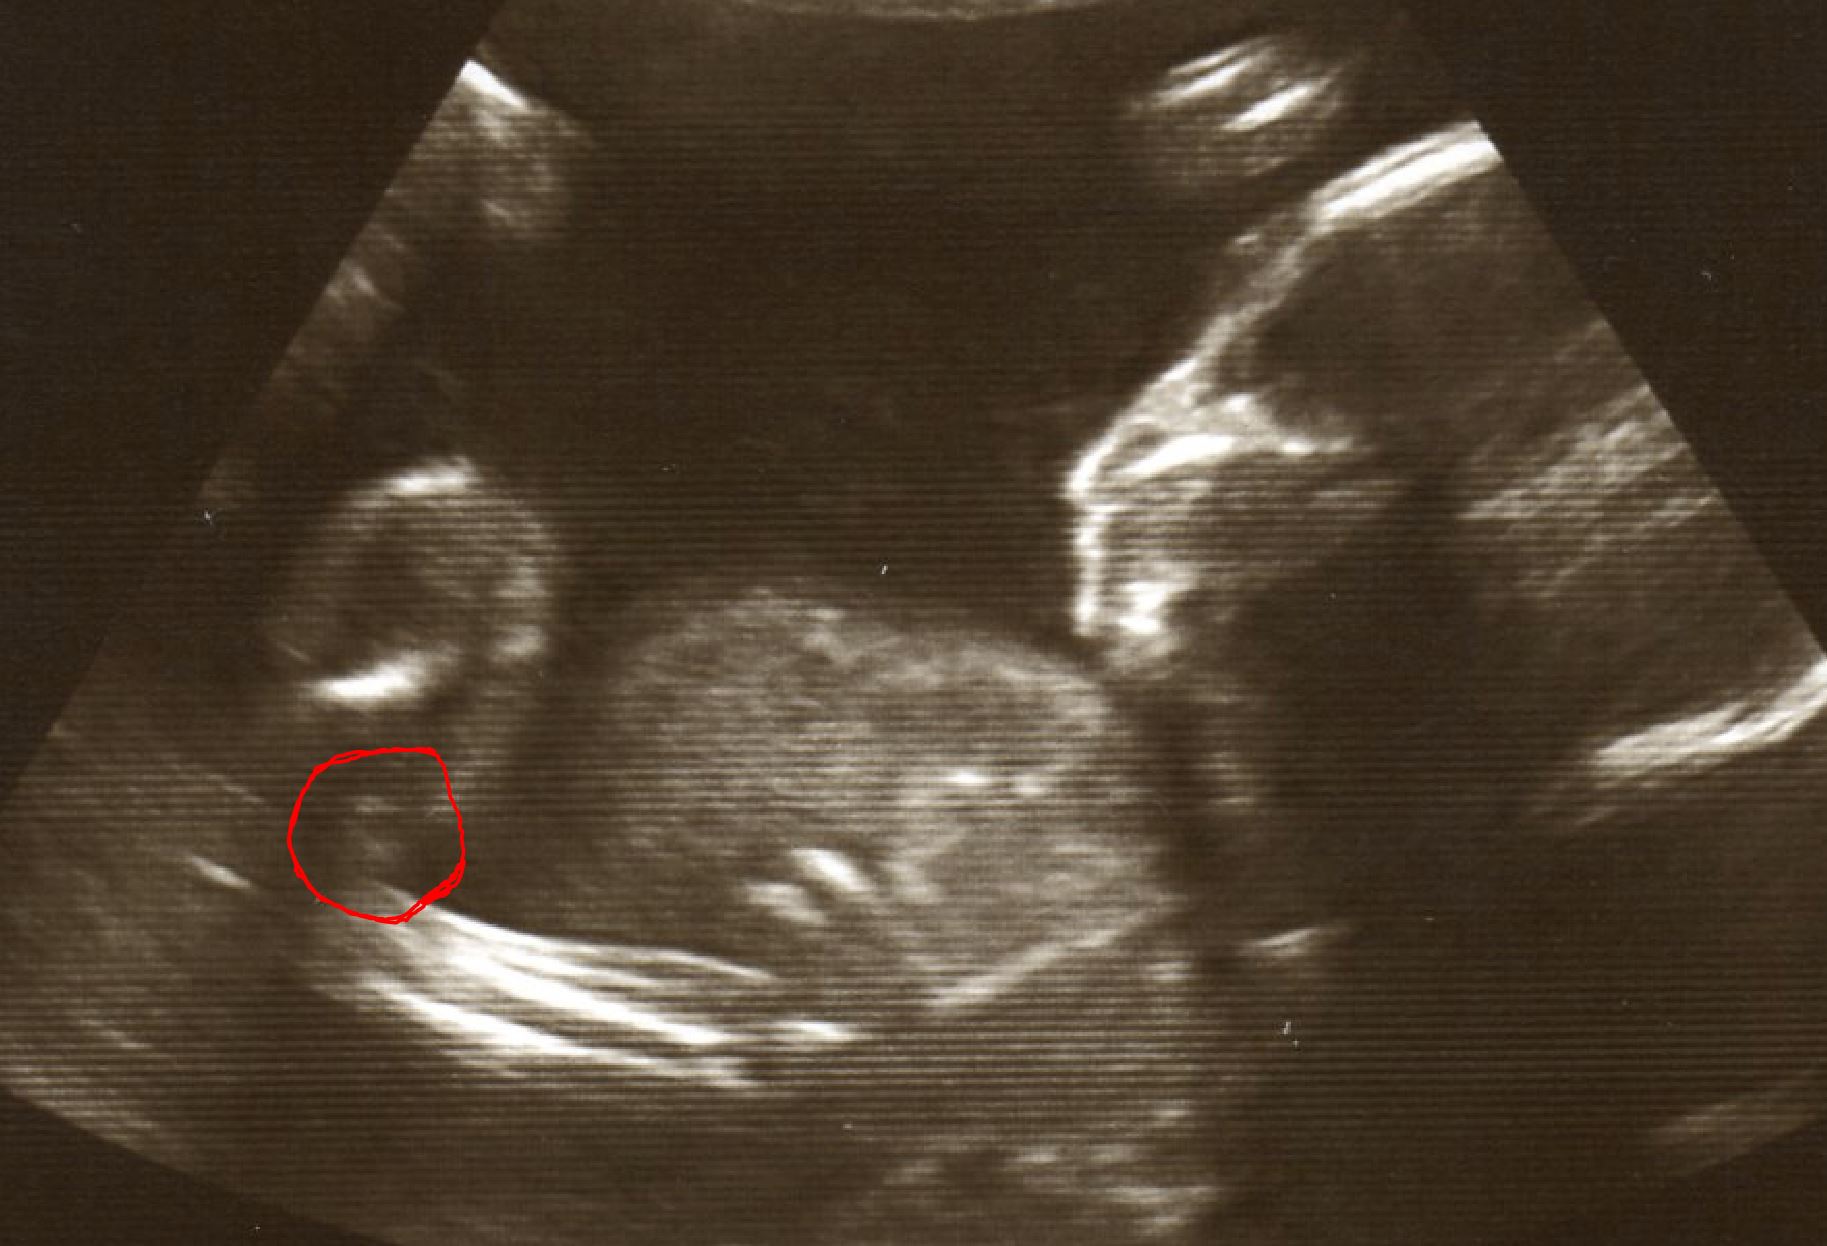

21 Week Scan Picture Girl?

Am really thinking this is a girl at 21 weeks I mean if you look in between the legs I think I see a virgina? the legs if that's what they are do seem to be in a awkward position because the scan shot is kinda from the side. I have circled what I think is the virgina with a red line to see a bigger picture right click on the picture and select "Open image in new tab" Please let me know what you think thanks.

Attachment 13160